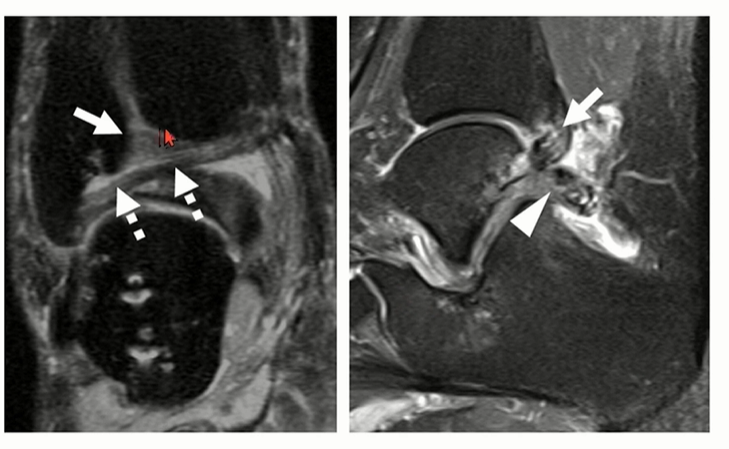

Ankle의 뒤쪽에는 여러 가지 ligment 구조가 있어서, posterior impingement의 원인이 될 수 있음,

1) PITFL, 2) inferior transverse 3) intermalleolar, 4) PTFL

(가장 좌측 그림에서 화살표로 표시됨. 위에서 아래 방향)

MRI상 ligament의 signal이 변화(좌측), thickening(우측)으로 관찰될 수 있다.